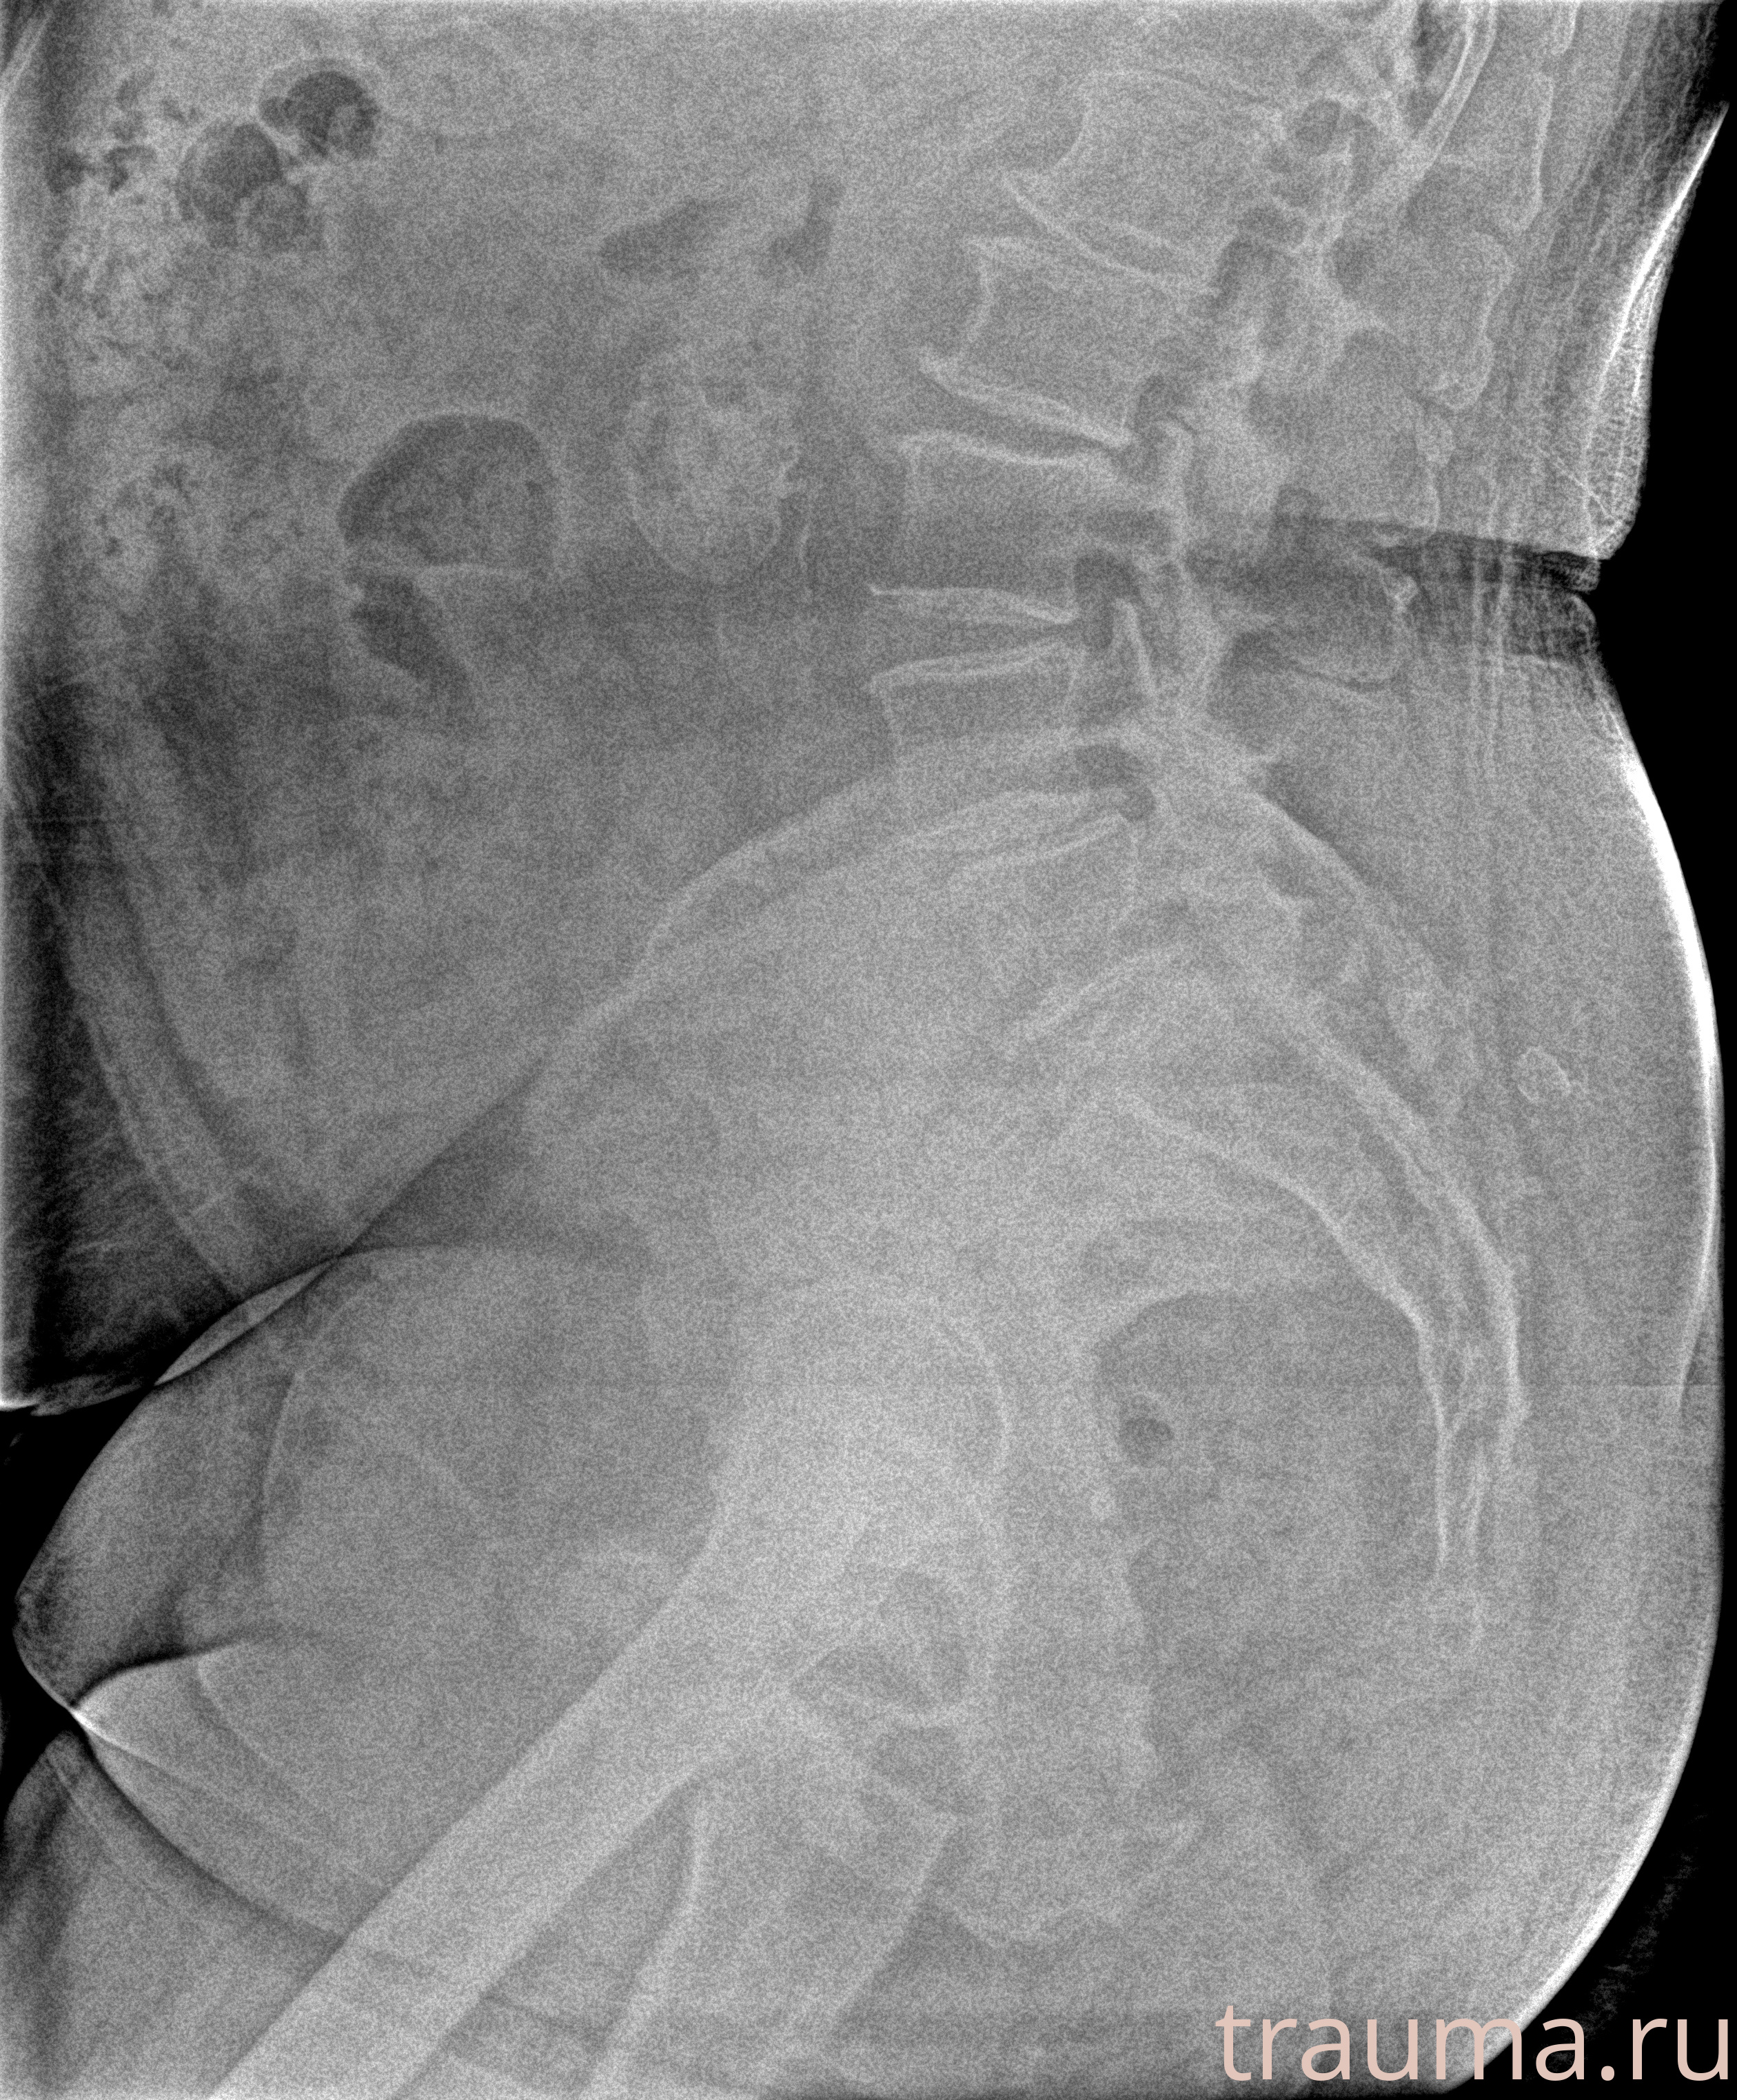

Рентгенограммы

Рентген на дому: по вашему адресу приезжает врач-рентгенолог, травматолог-ортопед с мобильным рентгеновским аппаратом, проводит диагностику травмы или заболевания, делает необходимые рентгенограммы, дает рекомендации по дальнейшему лечению. Получить качественные снимки в домашних условиях возможно благодаря уникальной методике, разработанной МосРентген Центром для института  Склифосовского